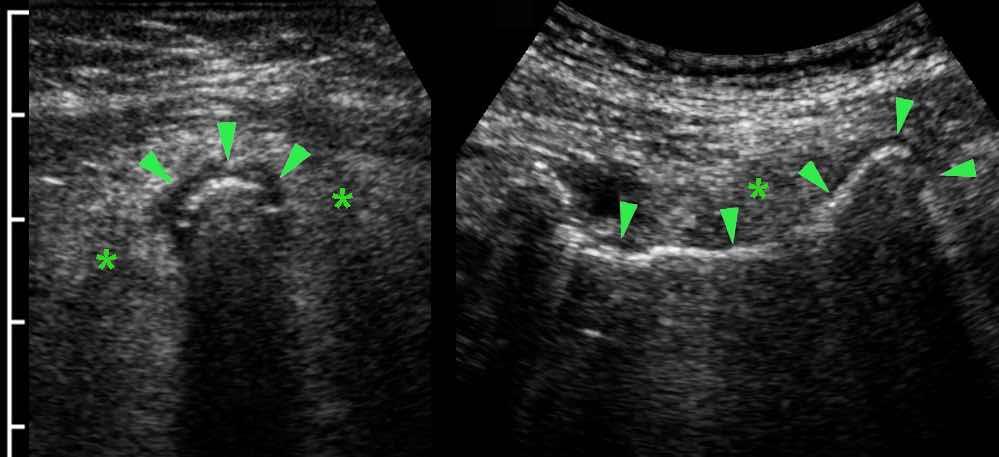

Hơi trong lòng ruột thừa có thể gây khó khăn trong việc xác định ruột thừa đang viêm (đầu mũi tên).

Thành ruột thừa giảm âm và lớp mỡ xung quanh đang viêm (*) cho thấy rõ ràng có viêm ruột thừa.